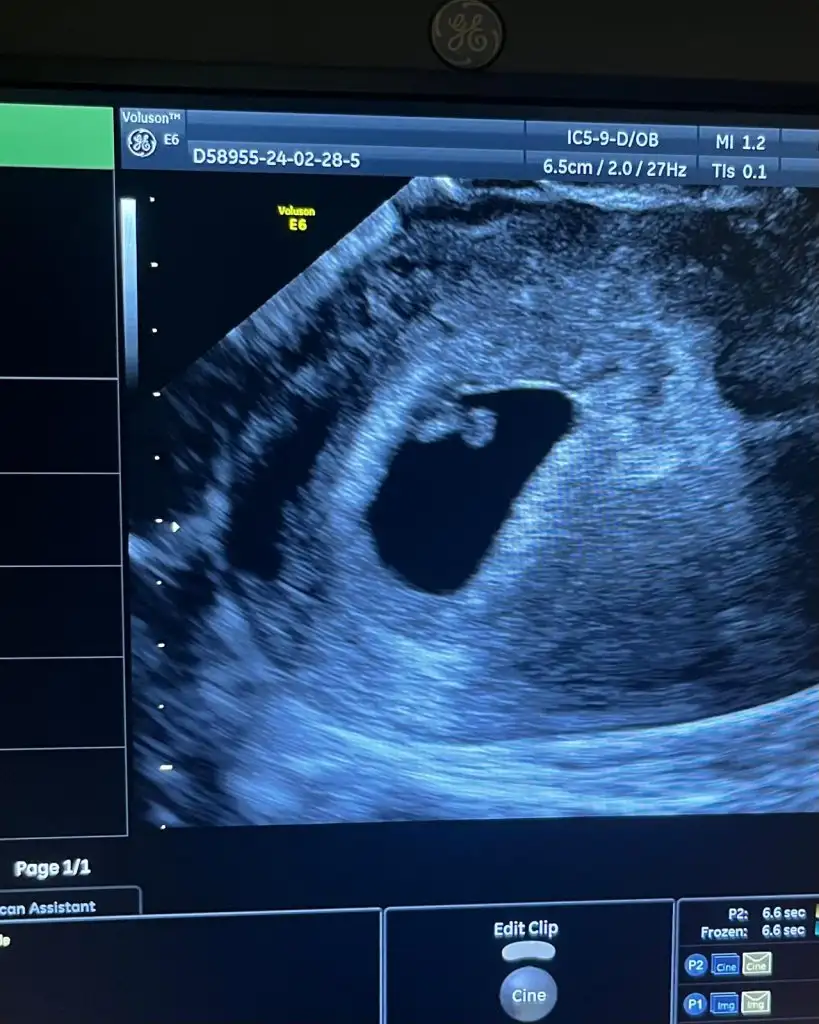

Ramzi teorisi okudum yüzde 97 dogruymuş.Ama neye göre bakcam ultrasona bilemedim. Size sormak istedim Bebeğim sağa daha yakın sanki bası da solda ayakları sağa bakıyor yani. Anlamadım ben. Sağlıklı olsun tabi kız erkek fark etmez ama merak ettim. İlk foto 5+5 iken 2.foto 9+3ken